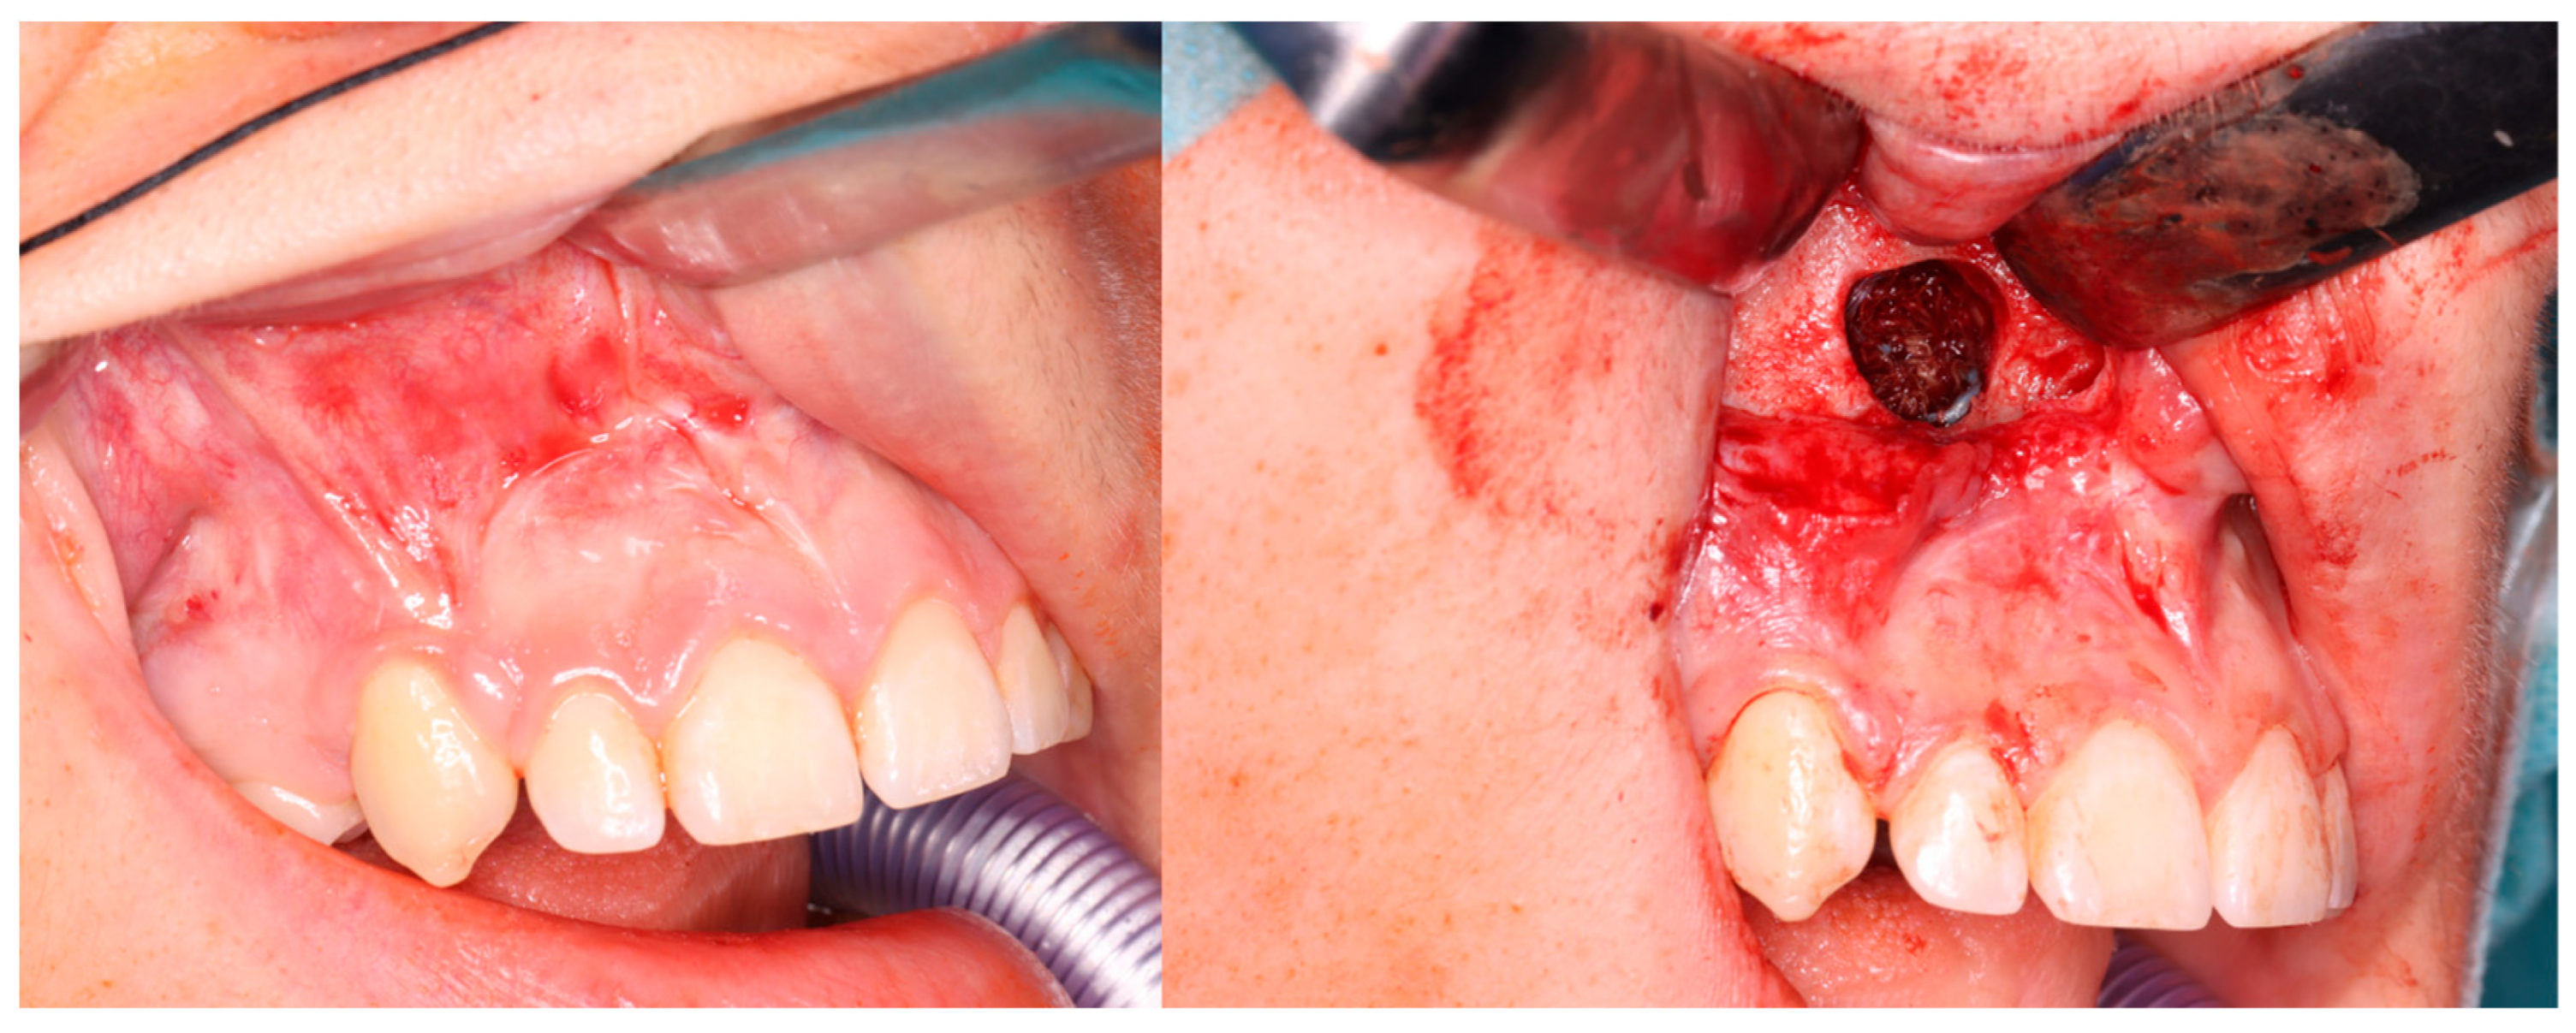

3. Results

3.2. Injections

4. Discussion